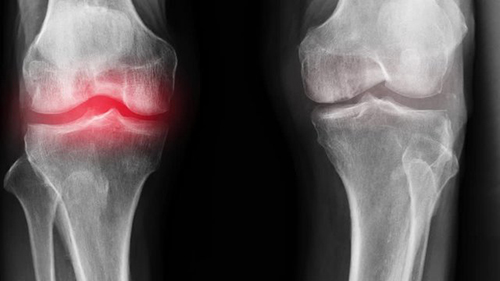

La causa principal del daño articular es la acumulación de cristales de sal en las articulaciones debido a una circulación sanguínea deficiente y a una mala circulación del líquido sinovial:

- Los cristales de urato son sales del ácido úrico que provocan la gota.

- Los osteofitos son sales calcificadas responsables del 97% de las demás enfermedades articulares y de la columna, como la artritis, artrosis, osteocondrosis, osteoporosis, reumatismo, bursitis e incluso quistes sinoviales.

Estas sales, al depositarse en la superficie de la articulación, actúan como papel de lija, dañando los tejidos circundantes, los huesos y el cartílago. A medida que los cristales crecen, comienzan a dañar los tejidos musculares, los tendones, los vasos sanguíneos y los capilares, provocando inflamación, infección, hinchazón y dolor intenso.